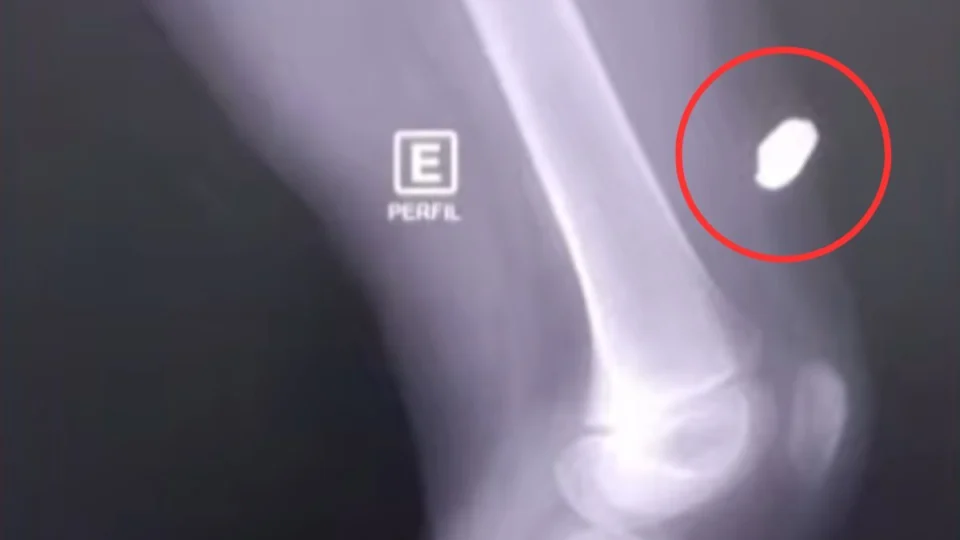

A Secretaria de Saúde do Amazonas (SES-AM) informou que atendeu a criança, que passa bem. O projétil ficou alojado na perna da vítima, mas ela não corre risco de morte.